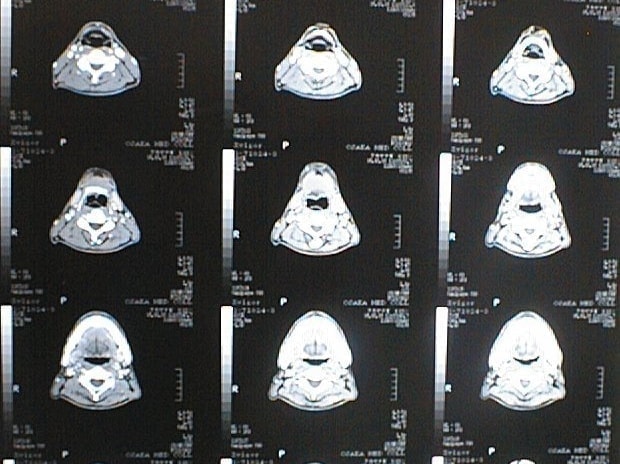

CT画像比較

中咽頭末期がんCT画像①

入院当時CT画像①

中咽頭末期がん消滅CT画像①

入院3か月後癌消滅CT画像①

中咽頭末期がんCT画像②

入院当時CT画像②

中咽頭末期がん消滅CT画像②

入院3か月後癌消滅CT画像②

中咽頭末期がんCT画像③

入院当時CT画像③

中咽頭末期がん消滅CT画像③

入院3か月後癌消滅CT画像③